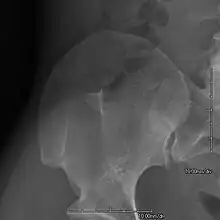

AP radiograph of the right iliac crest showing a bony exostosis or posterior iliac horn, which is pathognomonic of NPS

• Exostoses arising from the posterior aspect of the iliac bones ("iliac horns") are present in as many as 80% of patients; this finding is considered pathognomonic for the syndrome.